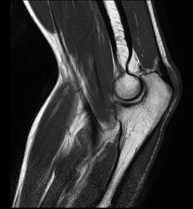

Exploración para el estudio de lesiones en la articulación, como roturas meniscales y de ligamentos cruzados (unicamente detectables mediante esta prueba), condropatía o desgaste del cartílago y multitud de otras alteraciones derivadas de la actividad deportiva y los cambios degenerativos (osteoartrosis). Tiene una duración aproximada de 18 minutos. No emplea radiación ionizante. - RM Pierna